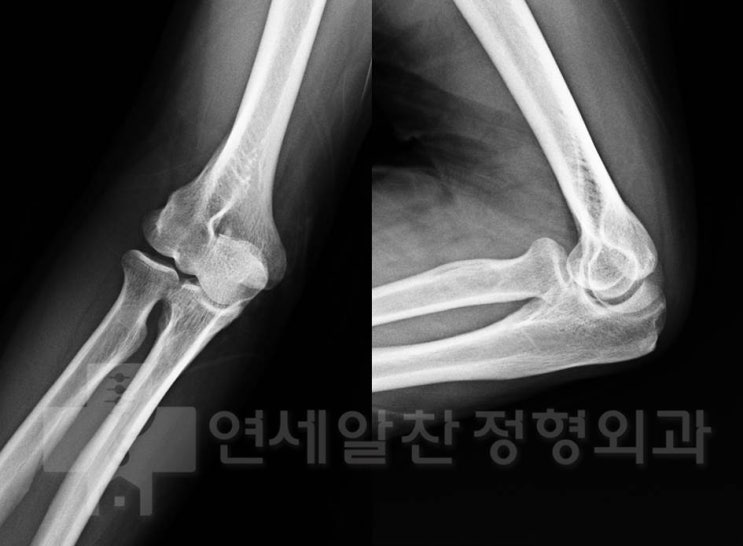

주관절 석회성 건염을 동반한 내측 총수지 굴곡건 파열에서 석회제거술 및 굴곡건 봉합술의 결과

42세 여자 환자로 본원에서 주관절 내측 석회성 건염으로 충격파치료를 시행하던 중 오랜기간동안 증상이 ...